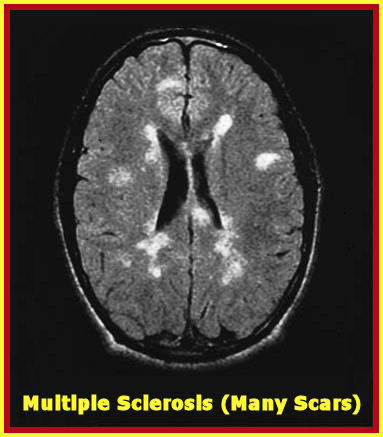

Segmentation Of Multiple Sclerosis Lesions In Brain MRI

University of Miami Scholarly Repository Open Access Dissertations Electronic Theses and Dissertations 2012-02-17 Segmentation of Multiple Sclerosis Lesions in Brain ... Fetch Document

Cerebral lesions Of Multiple Sclerosis: Is Gadolinium Always ...

Cerebral lesions of multiple sclerosis: is gadolinium always irreplaceable in assessing lesion activity? Constantina Andrada there is a sustained need for research to find better MRI markers of with ring-enhancing brain lesions can help to differentiate pathology. Neurora-diology ... Fetch Document

Demyelinating Disease And - Sehati

143 Demyelinating Disease and Brain Atrophy Multifocal White Matter Lesions. Multiple sclerosis . Hypertension and Increases with age, and has also been seen with ... Fetch Content